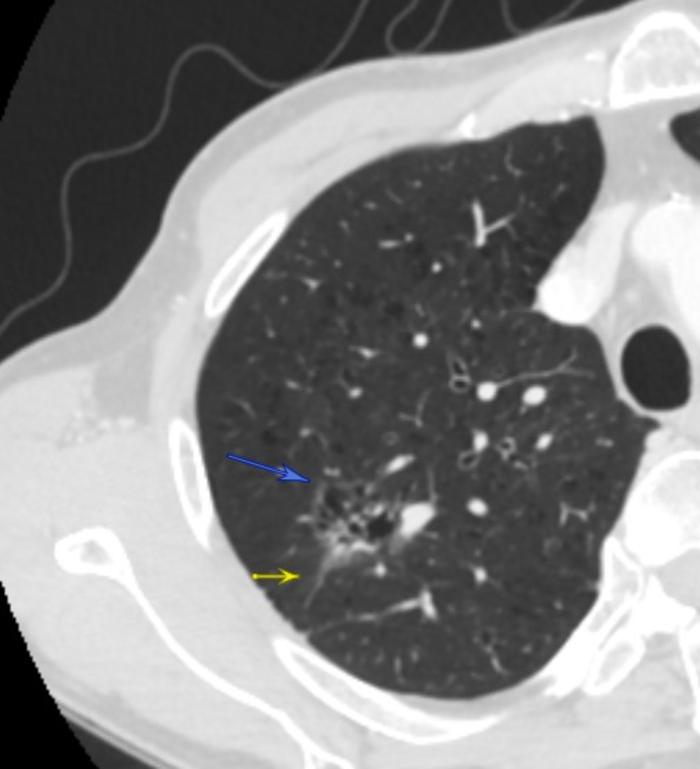

病例1:磨玻璃结节内部为蜂窝状结构

内部蜂窝状结构

这两张CT是同一个患者的混合磨玻璃结节,28×23毫米。第一张照片的黄色箭头可见边缘长毛刺影。第二张照片的两个蓝色箭头指示的是磨玻璃结节的灰色边缘,就是结节的磨玻璃成分。发白的部分是结节的实性成分。两张图内部可见蜂窝状磨玻璃成分。

病理是浸润性腺癌,两种亚型较好。